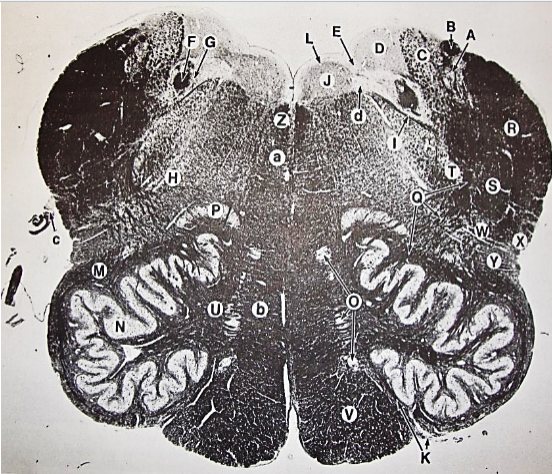

A

posterior median sulcus

B

posterior intermediate sulcus

C

anterior median fissure

D

gracile fasciculus

E

Gracile nucleus

F

fasciculus cuneatus

G

spinal trigeminal tract

H+I collectively

spinal trigeminal nucleus

J

Accessory nucleus

K

pyramidal decussation

L

lateral corticospinal tract

M

rubrospinal tract

N

posterior spinocerebellar tract

O

anterior spinocerebellar tract

P

lateral spinothalamic tract

Q

anterior spinothalamic tract

R

lateral vestibulospinal tract

S

medial longitudinal fasciculus

T

tectospinal tract

U

central canal